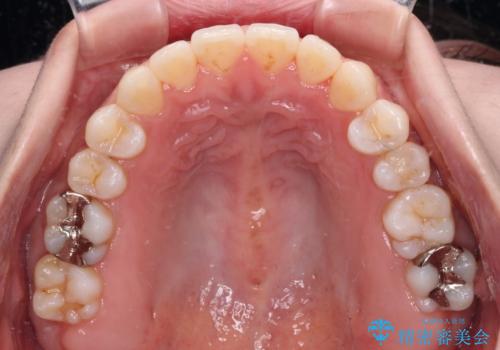

- 前歯の上下スペースと前歯の隙間を気にして来院された患者様です。

インビザラインにより上下の前歯の隙間を閉じていくこととしました。

上下の隙間に舌が入り込むことが、すきっ歯やオープンバイトの原因であったため、舌の筋肉のトレーニングも並行して行い、後戻りの抑制を図りました。